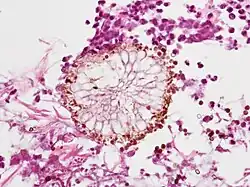

On microscopy, Aspergillus species are reliably demonstrated by silver stains, e.g., Gridley stain or Gomori methenamine-silver.[22] These give the fungal walls a gray-black colour. The hyphae of Aspergillus species range in diameter from 2.5 to 4.5 µm. They have septate hyphae,[23] but these are not always apparent, and in such cases they may be mistaken for Zygomycota.[22] Aspergillus hyphae tend to have dichotomous branching that is progressive and primarily at acute angles of around 45°.[22]

Angioinvasive pulmonary aspergillosis -

Angioinvasive pulmonary aspergillosis (closeup) -

Aspergillus vesicle (HE stain) -

Angioinvasive aspergillosis demonstrating the gross pathology equivalent of the CT ground glass halo